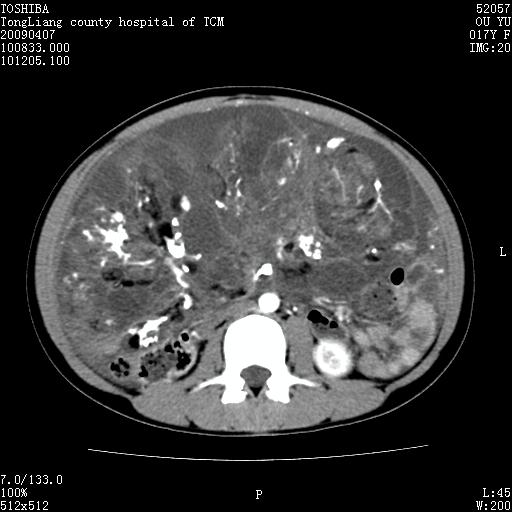

女,17岁,腹胀1月,b超示腹腔内巨大占位病变,腹水;

ct示腹腔内不均匀软组织肿块影,可见多数钙化灶(ct值400--800).周围肠管推移.

增强后,肿块内软组织不均匀强化,病灶内钙化灶边缘可见脂肪密度,肿块有包膜.向下与达盆腔.

腹部巨大紊杂密度肿块,边界不清楚,内有密度不均的软组织,多发不均匀钙化,钙化周围可见脂肪密度影,腹腔内可见积液及肿块内亦见液密密度区.增强后肿块内实质部分不均匀强化.钙化灶边缘脂肪灶显示更清楚.肠腔明显受推移.考虑畸恶性胎瘤.